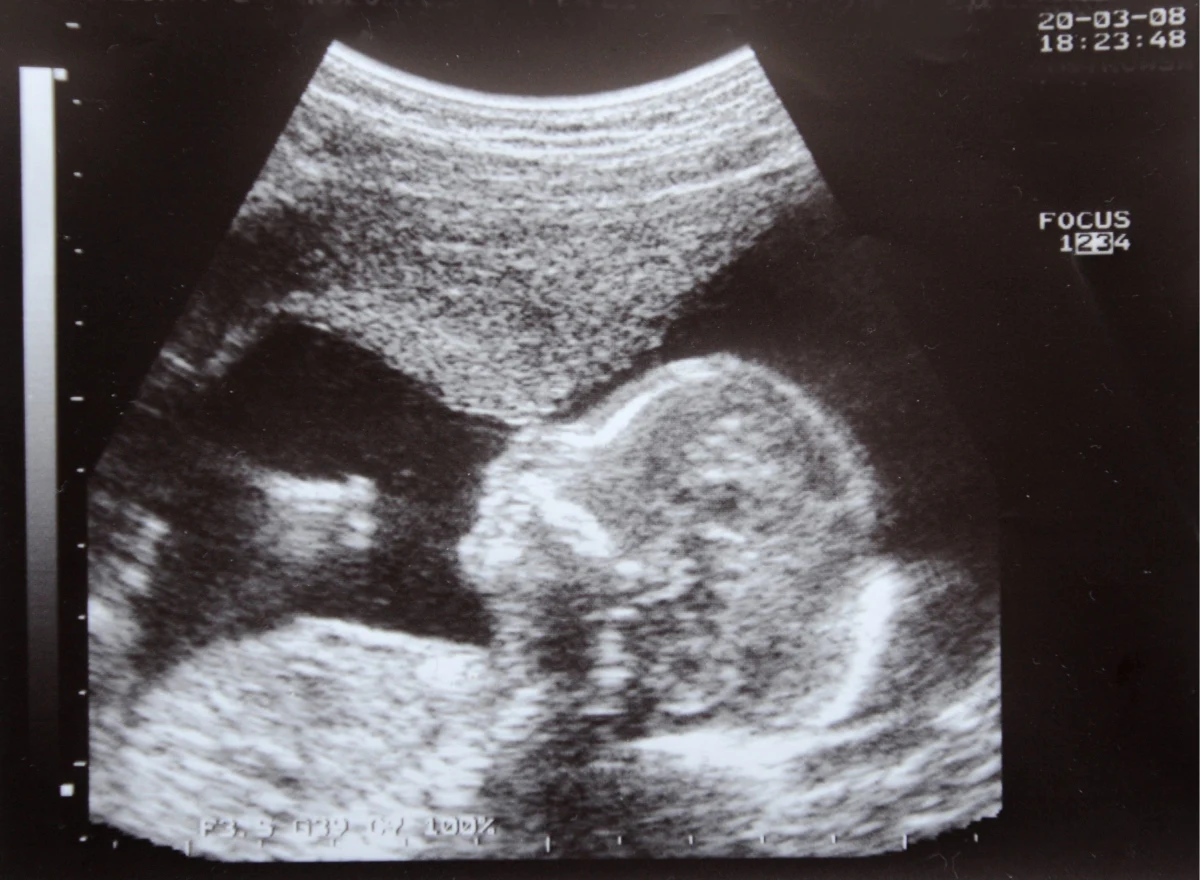

Stwierdzenie ciąży biochemicznej nie oznacza jeszcze, że przekształci się ona w tzw. ciążę kliniczną, w której w obrazie USG można znaleźć pęcherzyk płodowy i zarejestrować bicie serca płodu. To jednak będzie można stwierdzić w pierwszych z tych przypadków już za kilka dni i tygodni.